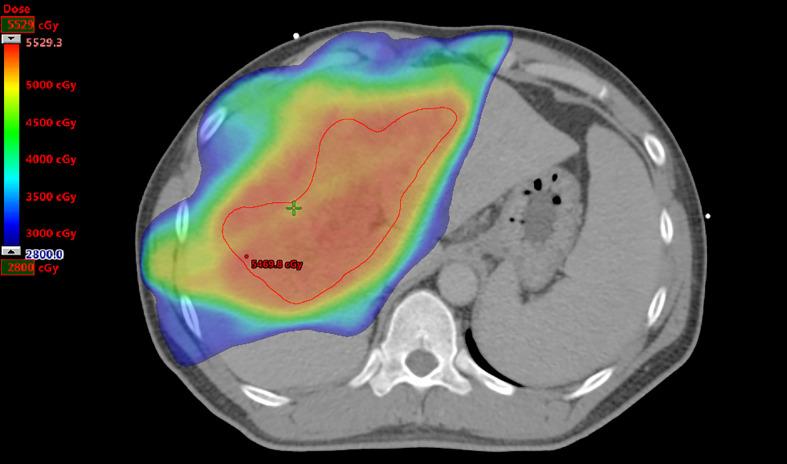

We retrospectively reviewed 131 patients. Patients were randomly divided into the training ( = 105) and validation ( = 26) cohorts. The clinical target volume was contoured on pre-RT computed tomography images and 48 textural features were extracted. The least absolute shrinkage and selection operator regression was used to determine the radiomics score (rad-score). A nomogram based on rad-score, clinical features, and dosimetric parameters was developed using the results of multivariate regression analysis. The predictive nomogram was evaluated using Harrell's concordance index (C-index), area under the curve (AUC), and calibration curve.

我们回顾性分析了131例患者。患者被随机分为训练组(n = 105)和验证组(n = 26)。在放疗前的计算机断层扫描图像上勾勒出临床靶体积,并提取48个纹理特征。采用最小绝对收缩和选择算子回归确定放射组学评分(rad-score)。利用多变量回归分析结果,建立了基于rad-score、临床特征和剂量学参数的列线图。使用Harrell一致性指数(C-index)、曲线下面积(AUC)和校准曲线对预测列线图进行评估。